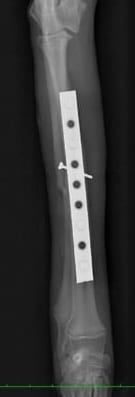

左前肢

左前肢は中和プレートのみなので2期癒合を目指します。

*術後早期は外固定を併用します。

同じく術後19日目 左前肢

左前肢は2期癒合を目指すので、術後2,3週間前後のレントゲンでは

周囲に仮骨形成を認め、また、

骨折部の骨が溶けているように見えます。

これは骨再構築(骨芽細胞、破骨細胞、両方の活動によるもの)

されて起こる現象なので問題ありません。

インプラントの折損、明らかな動揺は認めません。